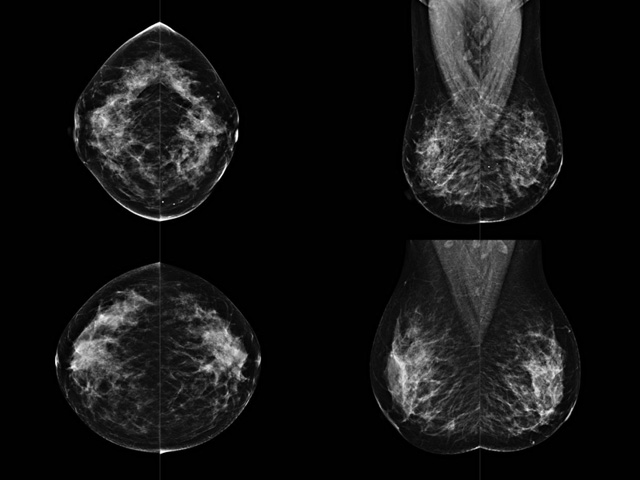

乳腺DR成像設(shè)備中非晶硅跟非晶硒兩種平板探測器

乳腺DR成像設(shè)備中非晶硅跟非晶硒兩種平板探測器。更要提供優(yōu)質(zhì)的圖像質(zhì)量乳腺的組織結(jié)構(gòu)與厚度各不相同,減少重拍率輻射劑量,,乳腺的主要構(gòu)成組織均為軟組織結(jié)構(gòu),組織之間密度十分相似,缺乏天然對比度。選擇軟X線攝影技術(shù)獲得良好對比度的乳腺結(jié)構(gòu)影像。增加各組織對X線的吸收差異。乳腺攝影測和分類,平板探測器的像素尺寸范圍應(yīng)在50到100μm之間。特別是微鈣化灶可以小到100到200μm,平板探測器都必極小微鈣化灶進(jìn)行成像。

乳腺DR是利用X光來做檢查,在一瞬間將被檢測到的位置投影出來,因?yàn)槭撬查g的輻射,所以只需要0.5秒的時(shí)間。因此對病人的輻射很低,大約是0.023mSv,比國家的標(biāo)準(zhǔn)要低得多。DR系統(tǒng)由 X線、發(fā)生裝置、直接轉(zhuǎn)換平板探測器、系統(tǒng)控制器、影像監(jiān)視器、影像處理工作站等組成。能檢查胸腔積液、肺結(jié)核、大葉性肺炎、肋骨骨折等。心室增大、主動脈擴(kuò)張、主動脈瘤等心臟病。腹部病變,如腸梗阻、腸穿孔等,DR上可見液氣平面、膈下游離氣腫。DR表現(xiàn)不正常,要結(jié)合臨床表現(xiàn)、體征、癥狀等綜合分析,結(jié)合CT、彩超、血液分析等,才能作出正確的判斷。